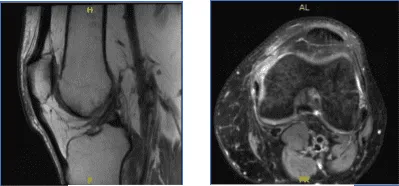

MRI-3T Left Knee Non-contrast

Results for MRI were presented and shown sprain of the medial collateral ligament, without evidence of high-grade tears. Longitudinal vertical tear involving the outer third of the body and posterior horn medial meniscus.